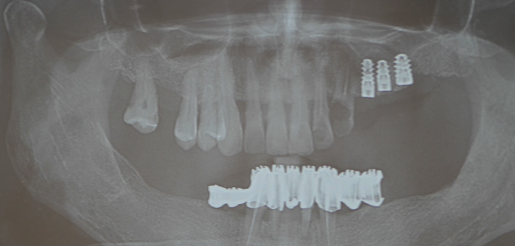

Pe baza scanărilor imagistice 3D (CBCT) se vor efectua măsurători ale înălțimii și lățimii osului mandibular, astfel încât medicul implantolog să poată decide dacă se pot insera implanturi direct sau este nevoie de adăugare de os în prealabil. Se realizează un ghid chirurgical care ajută la poziționarea precisă a implanturilor în os (Fig.3.6.4. dr. Ondine Lucaciu), iar în 24 de ore după această intervenție pacientul primește o punte provizorie fixă pe care o va purta un interval de 3-6 luni, perioadă necesară osteointegrării implanturilor, respectiv vindecării (Fig. 3.6.5). Această lucrare provizorie va fi înșurubată în 6 puncte, în cele 6 implanturi inserate în mandibulă (Fig. 3.6.6).